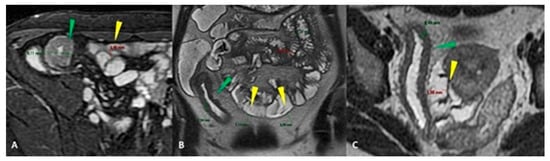

- Guglielmo, F.F.; Anupindi, S.A.; Fletcher, J.G.; Al-Hawary, M.M.; Dillman, J.R.; Grand, D.J.; Bruining, D.H.; Chatterji, M.; Darge, K.; Fidler, J.L.; et al. Small Bowel Crohn Disease at CT and MR Enterography: Imaging Atlas and Glossary of Terms. Radiographics 2020, 40, 354–375. [Google Scholar] [CrossRef]

- Griffin, N.; Grant, L.A.; Anderson, S.; Irving, P.; Sanderson, J. Small bowel MR enterography: Problem solving in Crohn’s disease. Insights Imaging 2012, 3, 251–263. [Google Scholar] [CrossRef] [PubMed]